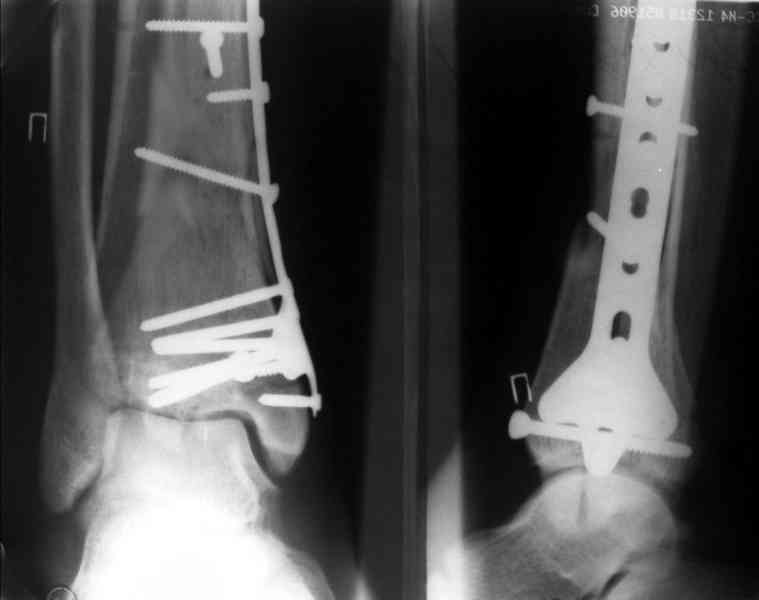

На рентгенограммах типичный перелом пилона по типу С-3. есть опыт до 100 открытых опреаций у нас в клинике. 20 примерно в год. Принцип один -все внутрисуставные переломы нуждаются в открытой репозиции и внутренней стабильной фиксации. При поступлении КТ не надо, так как получается только нагромождение костей. Истинной картины нет. Главное восстановить длину малоберцовой кости - это ключ к успеху. При поступлении меньше всего надо думать о сосудистых расстройствах, т.к. сама операция и репозиция даже сначала частичная даёт улучшение сосудитых нарушений. Причём очень быстро. Операция в 2этапа. При поступлении доступ позади наружной лодыжки, причём обязательно. После этого репозиция малоберцовой кости и фиксация пластиной 1/3 трубки под винт 3,5. Дренаж и любой аппарат наружной фиксации. Затем после спадения отёка на 5-7-10 день аппрат снимается и дугообразный разрез спереди от медиальной лодыжки 10-12 см. Главной чтобы расстояние между 1 и вторым разрезом было не меньше 7-8 см. Тогда не будет некрозов лоскутов. Таранная кость используется как матрица на неё укладываются отломки и фиксируются пицами. Ренг-контроль. Отломки лежат все отдельно, но ничего не высыпется. При переломах С-3 всегда нужна костная пластика (из крыла). Фиксация пластиной лист клевера простой или LCP. Гипс не нужен. Дренаж до 48 часов. Операция длится 3-4 часа обязательно без жгута. Посылаю примерно такой же случай.

Посылаю результат лечения предыдущего больного через год.

С уважением Дрягин